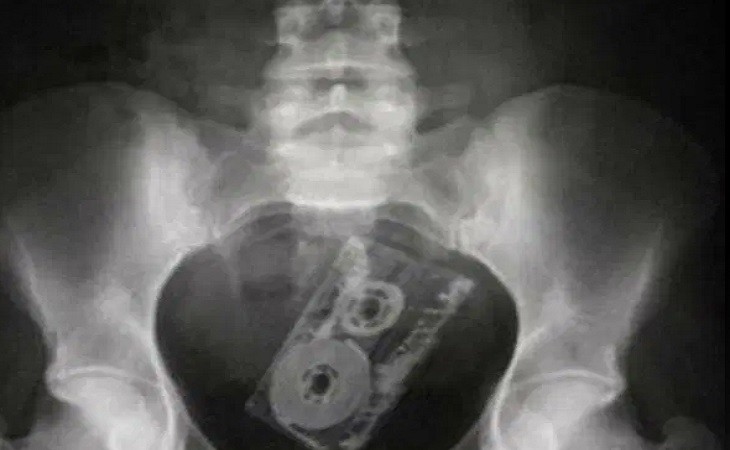

Но лидируют в данном списке, по понятным причинам, секс-игрушки. Один из врачей предложил продавать подобные вещи со специальными шнурами для удаления, чтобы облегчить труд медицинских работников. При этом доктора добавили, что секс-игрушки безопаснее, чем различные предметы из бытового обихода.

В большинстве случаев посторонние предметы врачам приходилось удалять хирургическим путем.